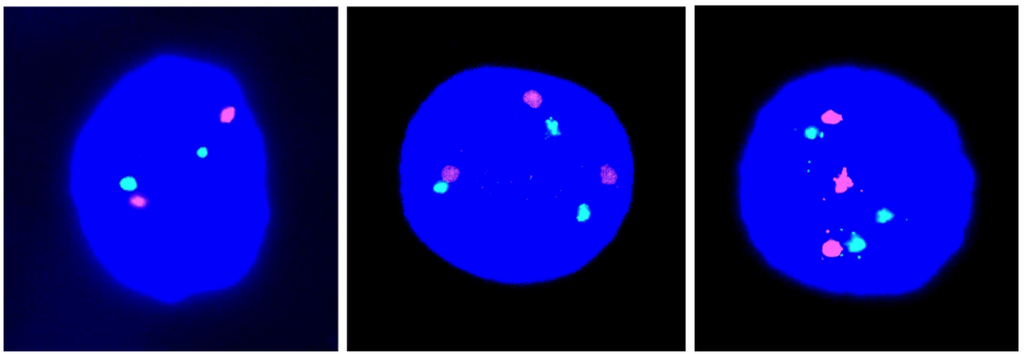

We have used FISH with two chromosome 21-specific probes, labelled in different colors (red and green) in order to assess the incidence of T21 in fetal ovaries obtained following TOP for a social reason at the clinical gestational age of 9–11 weeks.

In this new series, we have recorded the incidence of T21 cell nuclei in 12 fetal ovarian samples, obtained during the first trimester of pregnancy. Examples of cell nuclei with T21 in comparison to the normal diploid are given in Figure 1. We identified a mean number of only 0.066% cell nuclei, showing T21 with a range of 0.00%–0.14% and an standard deviation (SD) of 0.045% in a total cell population of 27,042 (Table 1). This result is highly statistically significantly different (p < 0.0001) from the results (average, 0.54%; range, 0.20%–0.88%; SD, 0.23) obtained in our previous investigation of eight cases, ascertained after TOP in the second trimester (Figure 2 in [6]).

Figure 1. Illustrations of cell nuclei containing a different chromosome 21 copy number: Two red-green signals indicative of disomy 21 (left) and three red-green signals indicative of trisomy 21 (middle and right).